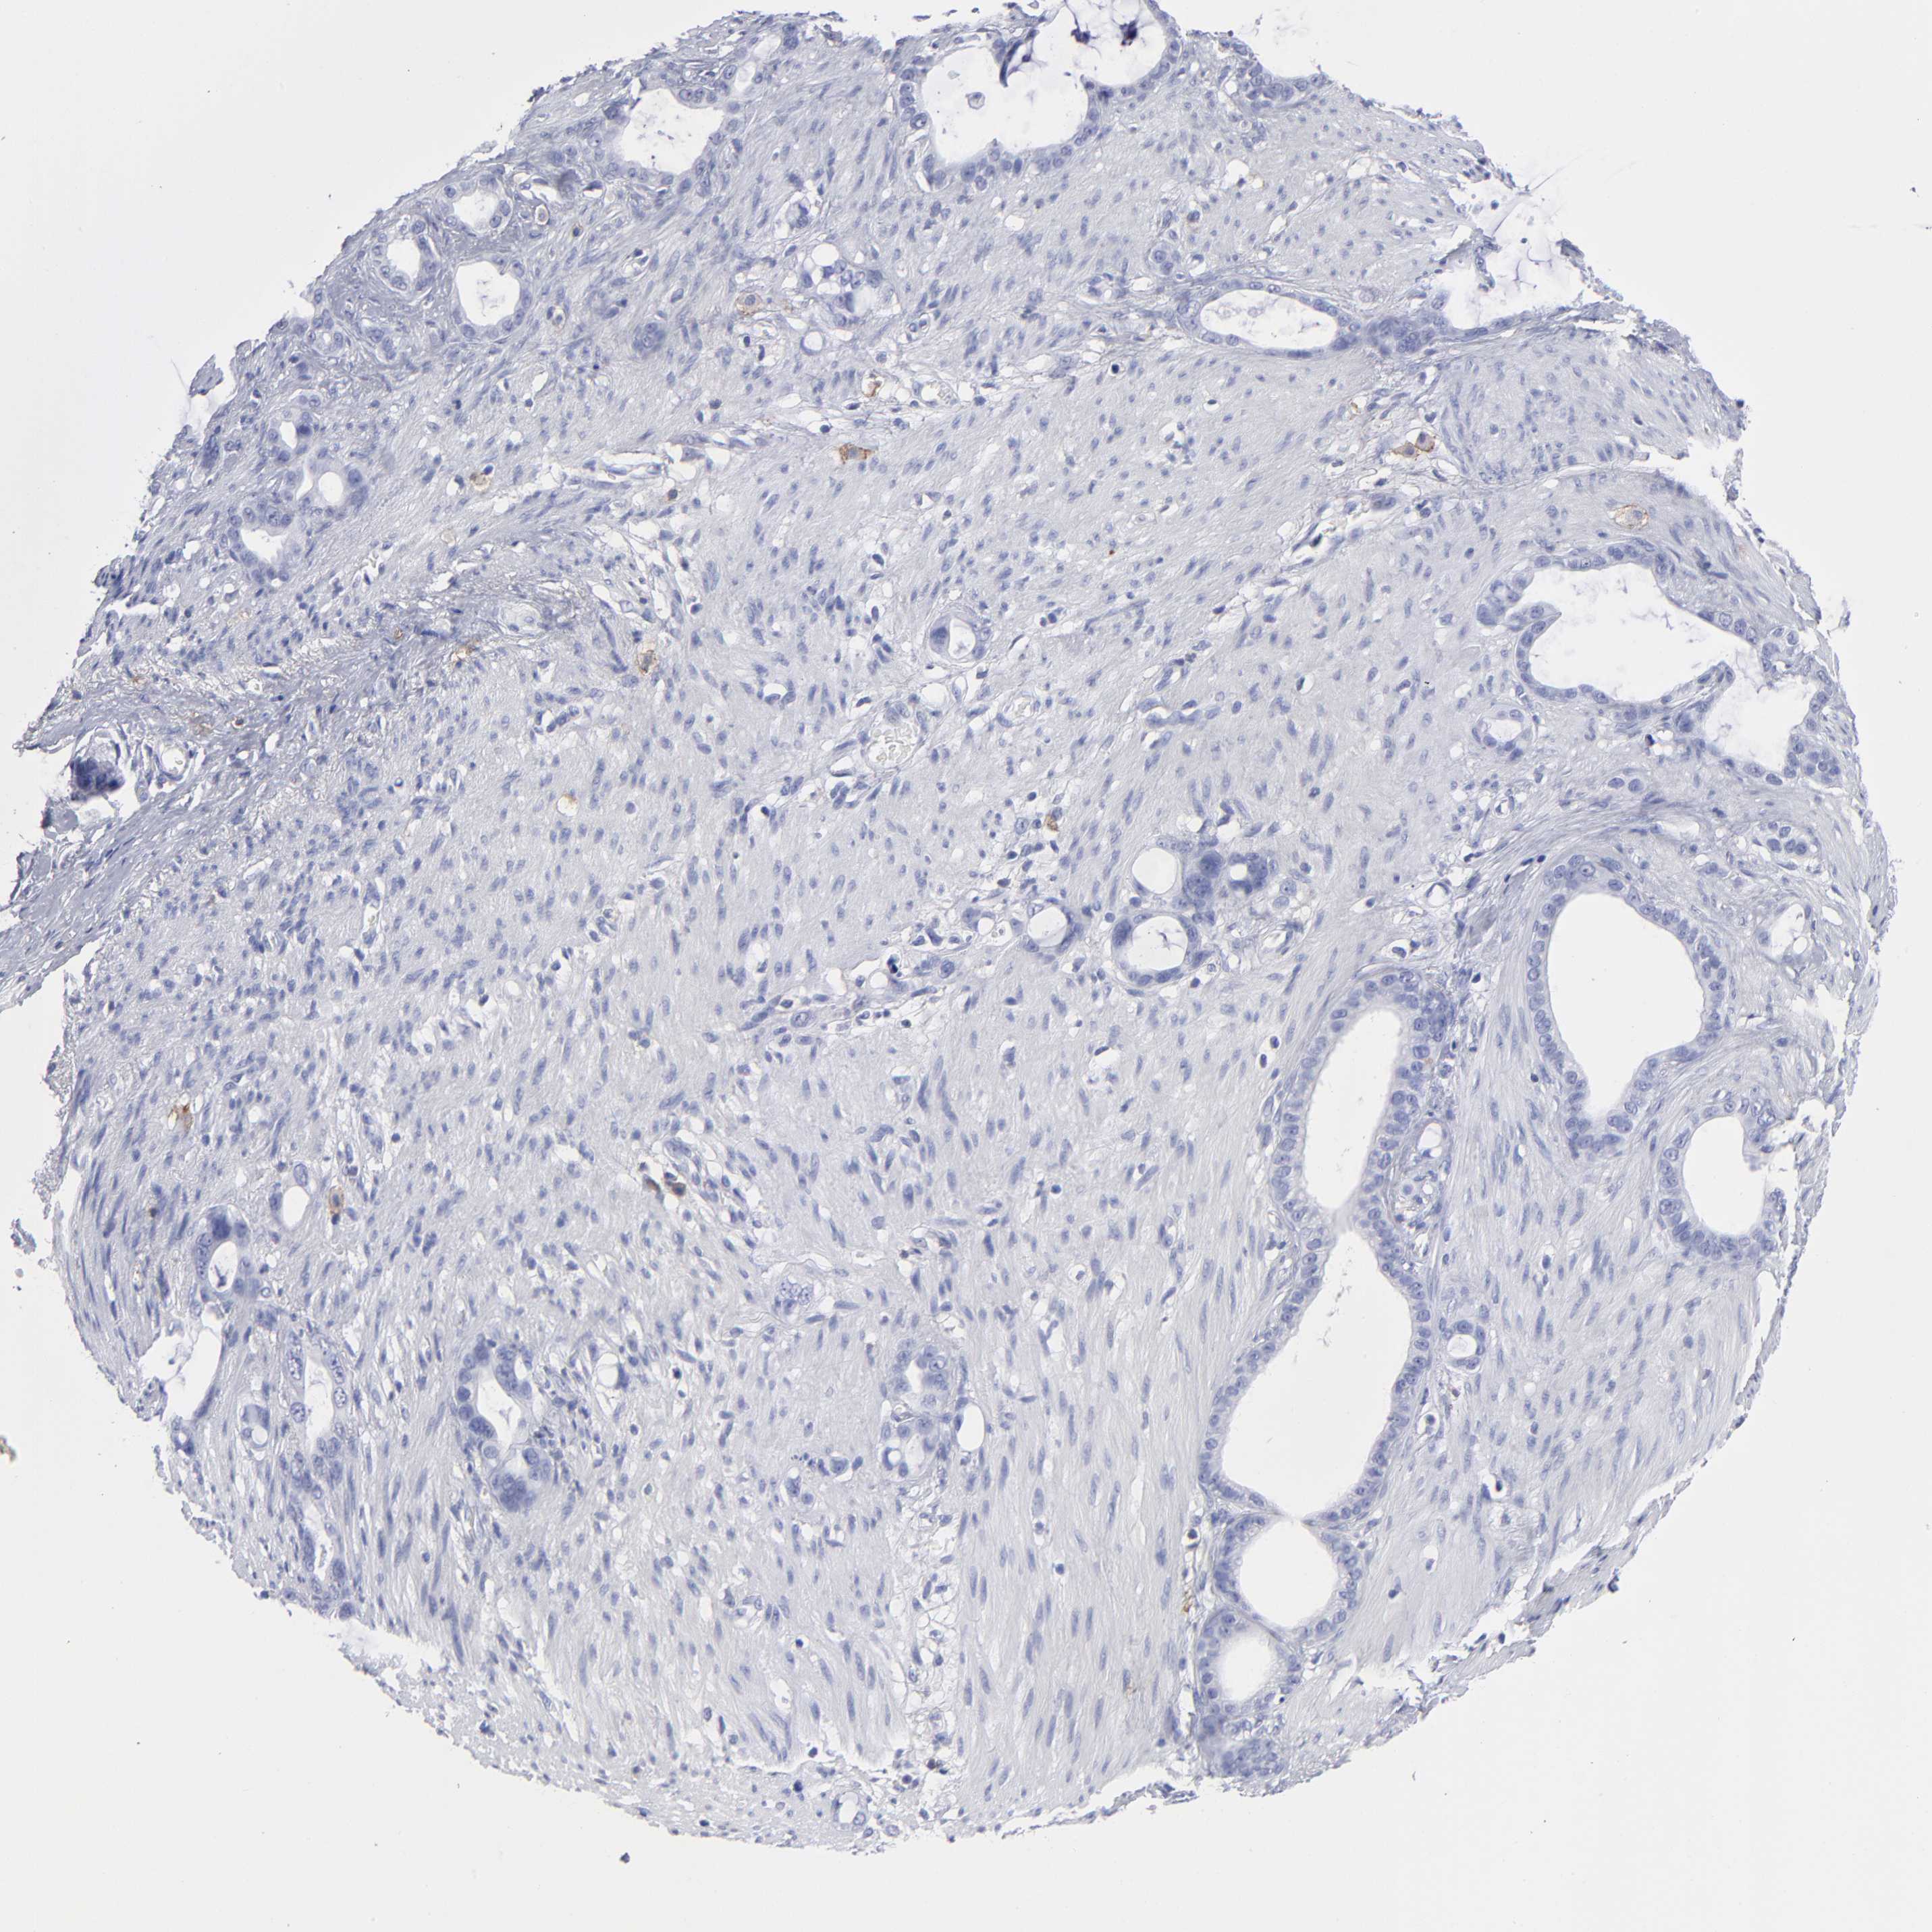

STOMACH CANCER - Protein expressioni

A mouse-over function shows sample information and annotation data. Click on an image to view it in a full screen mode. Samples can be filtered based on level of antibody staining by selecting one or several of the following categories: high, medium, low and not detected. The assay and annotation is described here.

Note that samples used for immunohistochemistry by the Human Protein Atlas do not correspond to samples in the TCGA dataset.

Antibody stainingi

Antibody staining in the annotated cell types in the current human tissue is reported as not detected, low, medium, or high, based on conventional immunohistochemistry profiling in selected tissues. This score is based on the combination of the staining intensity and fraction of stained cells.

Each image is clickable and will lead to virtual microscopy that enables deeper exploration of all samples and also displays staining intensity scores, fraction scores and subcellular localization as well as patient and tissue information for each sample.

Antibody HPA003462

Staining

High

Medium

Low

Not detected

Intensity

Strong

Moderate

Weak

Negative

Quantity

>75%

75%-25%

<25%

None

Location

Nuclear

Cytoplasmic/membranous

Cytoplasmic/membranous,nuclear

Adenocarcinoma, NOS

Adenocarcinoma, High grade